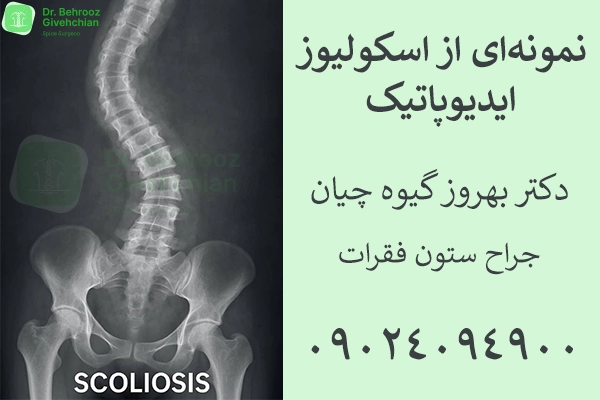

اسکولیوز به انحنای غیرطبیعی ستون فقرات در نمای قدامی گفته میشود. برخلاف بسیاری از افراد که فکر میکنند فقط «کجی» دیده میشود، اسکولیوز اغلب با چرخش مهرهها همراه است. واژه اسکولیوز از کلمه یونانی skolios به معنی کج یا انحنادار گرفته شده است.

• اسکولیوز ایدیوپاتیک (Idiopathic Scoliosis)

شایعترین نوع اسکولیوز در کودکان و نوجوانان است و علت مشخصی برای آن وجود ندارد (خود کلمه ایدیوپاتیک به معنای “بیعلت” است). این نوع انحراف ستون فقرات در سنین بلوغ (۱۰ تا ۱۸ سال) رخ میدهد و به دلیل عوامل ژنتیکی و ارثی احتمال بروز آن افزایش مییابد. پیشرفت اسکولیوز ایدیوپاتیک تدریجیست و در مراحل اولیه بدون علامت بوده و تنها با معاینات دورهای یا مشکلات ظاهری مانند نابرابری شانهها یا کمر مشخص میشود.